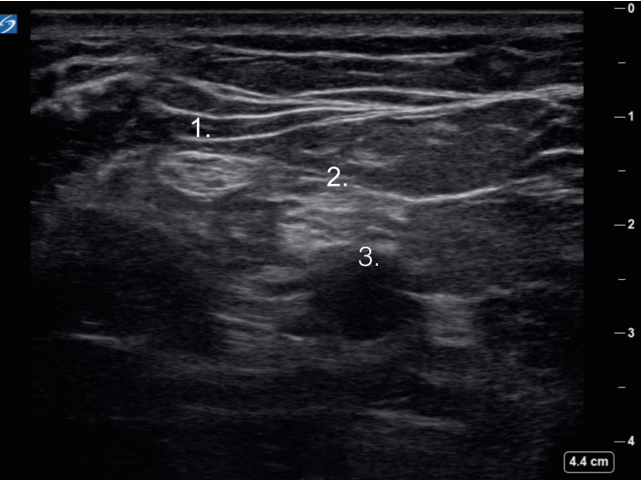

Popliteal Scanning Technique 4 Image

Common Peroneal Nerve

Tibial Nerve

Popliteal Artery